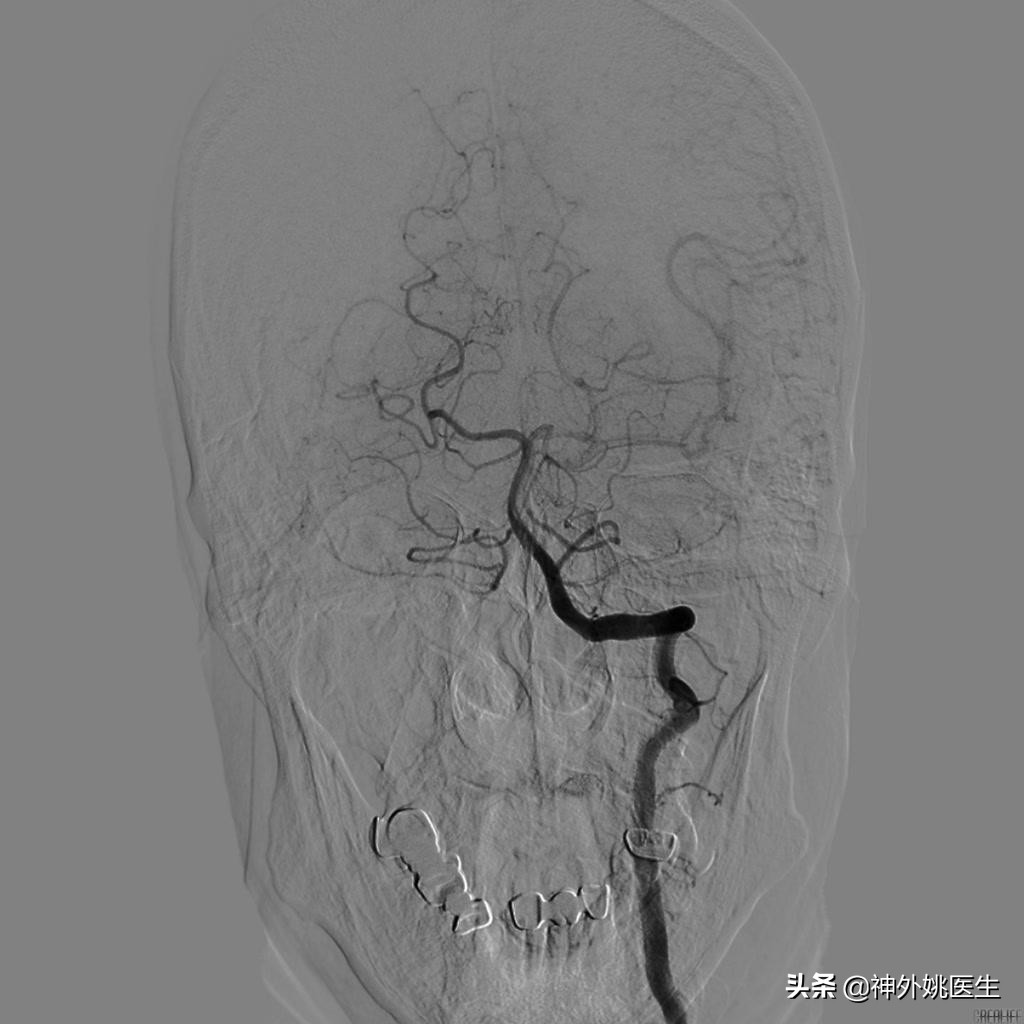

术前DSA检查:(图3-6)

图3 左颈内动脉起始段重度狭窄。

图4 右颈动脉造影示前交通动脉开放,左侧A2以远显影,通过左侧A1至M1以远亦显影。

图5 左侧颈动脉造影示左侧大脑前动脉显影欠佳。

图6 椎基底动脉造影示左侧后交通动脉开放,左侧大脑中动脉显影。